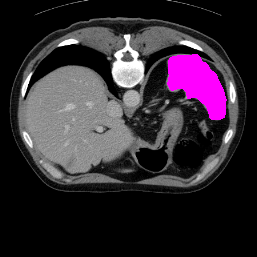

Support

Label

Proposed

In order to assess the performance of the proposed method, we compare the performance of the proposed model with excellent models in recent years. Table 1 and Table 2 shows the comparison results of different models in setting1, while Table 3 and Table 4 shows the comparison results of different models in setting2 on the data set in recent years. PANet[25] is the most widely influential few-shot model in the field of few-shot image segmentation on natural images. SENet [18] is the first few-shot segmentation model proposed for medical images. SSL-ALPNet[19] introduced the milestone of using superpixel self-supervision to train few-shot medical image models. RPNet[29] is a supervised method with a recursive mask optimization module to iteratively optimize the segmentation mask, [27] adapt it into the same self-supervision learning framework and applies setting1 to it and denoted as SSL-RPNet; CRAPNet[27] is the latest SOTA model for 2023. Compared with CRAPNet, our method outperforms most of the state-of-the-art models and only slightly outperforms CRAPNet. Figures 3 and 4 show examples of the model’s segmentation predictions on different datasets, respectively; The first row is the support map, the second row is the label map, and the third row is the segmentation prediction of the model.